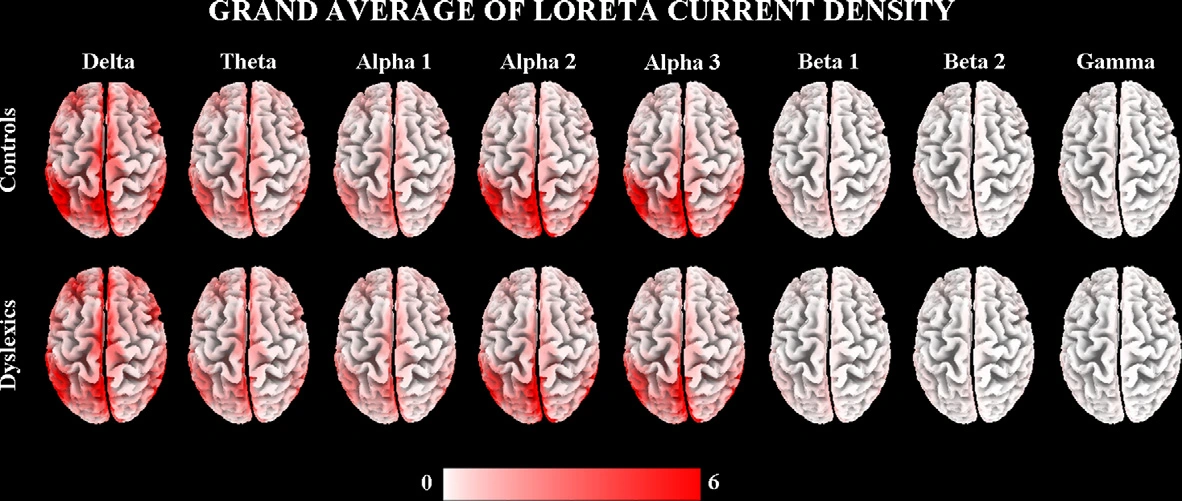

Le Sorgenti Corticali dei Ritmi EEG a Riposo Sono Anomale nei Bambini con Dislessia

Nei bambini dislessici, i ritmi EEG alfa a riposo mostrano un’attività ridotta nelle aree posteriori del cervello, suggerendo un’alterazione dei meccanismi di sincronizzazione neuronale coinvolti nei processi fonologici e nelle abilità di lettura.